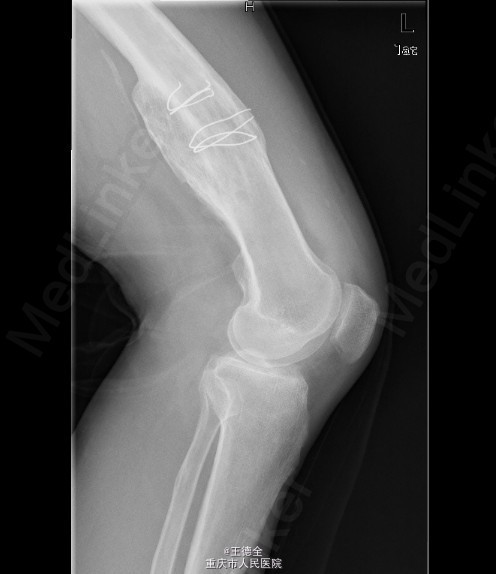

患者男,40岁,因“左股骨下段骨折术后4+年,左膝反复肿痛2年余”入院;自诉于4年前不慎被石块砸伤左大腿,伤后即觉左大腿疼痛,流血,左下肢活动障碍,患者伤后即到当地医院就诊,诊断为:"左股骨下段开放性骨折",予骨折切开复位内固定术,术后3个月下地行走,术后内固定螺钉松动、脱落,近两年来出现左膝关节肿胀、疼痛,活动时肿胀、疼痛症状加重,无畏寒发热、肢端麻木等,患者病后曾到当地医院就诊,予服药治疗后症状无明显好转,为进一步诊治遂来我院就诊,门诊拟"左膝骨性关节炎"收住我科,病程中,患者一般情况尚可,睡眠、饮食可,大小便正常,体重无明显改变。

查体:生命体征平稳,心肺腹未见异常;膝关节周围课件明显肿大,左膝关节活动受限,皮温略高;左股骨下端可扪及肿大,腘窝有一处大小约5x4cm的肿块,辅查x线片如下。